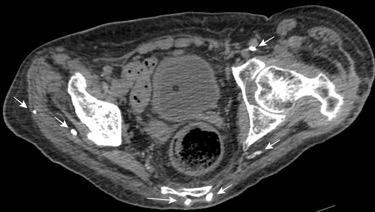

10-20% de pacientes las larvas alcanzan la circulación sistémica y pueden llegar a cualquier órgano También pueden llegar a órganos intrabdominales por migración transmural.

Yagmur Y et al. Unusual Location of Hydatid Cysts: A Case Report and Literature Review. Int Surg. 2012 / Pedrosa I et al. Hydatid disease: radiologic and pathologic features and complications . Radiographics 2000.